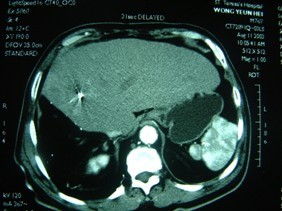

笔者所在医院曾治疗一位94岁老人张XX女士。2004年她突然感到背痛逐日加剧。儿孙带她到某医院看病,CT检查发现为肺癌,已转移到脊椎骨,疼痛系由肿瘤压迫神经所致。医生问她多大年龄啦?儿孙回答94岁,医生大吃一惊,自言自语说:“94岁,我能活这么长就好了”。随之开了12片止痛药,嘱她儿孙带回家“好好孝顺”。但老人背痛一天天加剧,终日呻吟不绝。儿孙带她到我们医院,我们为她做了冷冻治疗。冷冻后三十分钟,疼痛就停止;一个月后,肿瘤缩小一半,现在几乎消失(图1)。老人今年已100岁有余,正在颐养天年。

图1(a)治疗前的CT显示右肺后段肿瘤,已侵犯脊椎骨;(b)治疗后半年复查,肿瘤大都消失;(c)张女士近况